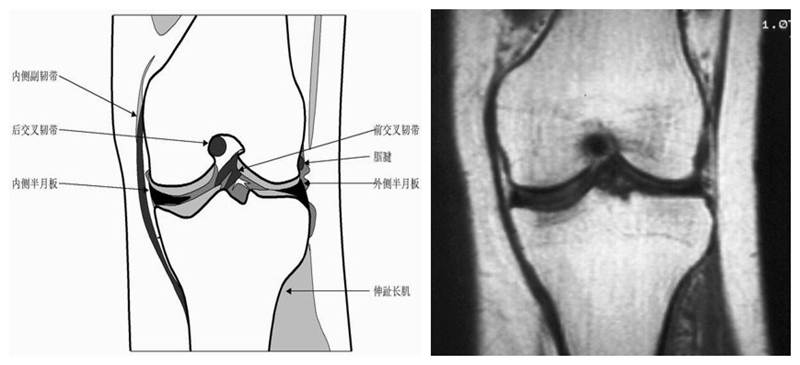

膝关节冠状面MRI解剖

显示内外侧副韧带、腘肌和拱状韧带,有无信号和结构改变,侧重关节胫股软骨的两边和半月板的体部。

冠状位解剖第一层